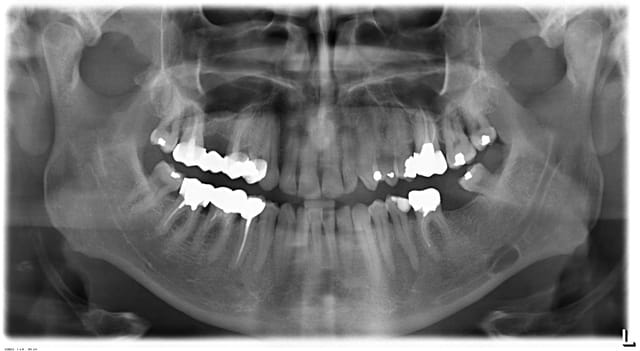

Dans la série des images radioclaires...Voici un patient de 56 ans venant pour la pose d'un implant au niveau de 37...

Découvert e fortuite à la panoramique d'une image radioclaire asymptomatique et non décelable cliniquement...

Diagnostic?

Conduite à tenir?

L'implant peut il tout de même être posé en 37?

Vu l'aspect radiographique, la localisation et ta description, c'est probablement une lacune de Stafne : un lobule de la glande submandibulaire qui s'est développé au détriment de la corticale linguale mandibulaire.

Refais une pano dans 2 et 6 mois pour être sûr de ne pas passer à côté de quelque chose.

Pareil, lacune de Stafne en première intention.

Fais faire un scan. tu dois avoir une image en encoche avec conservation de la corticale vestibulaire.

Il n'y a aucun traitement à envisager pour ça, c'est une variation de la normale avec un contrôle dans 6 mois voire un an pour être sûr.

Pour l'implant je pense que tu peux y aller sans problème. En plus, tu as des kilomètres d'os au dessus de ton image pour poser ton implant